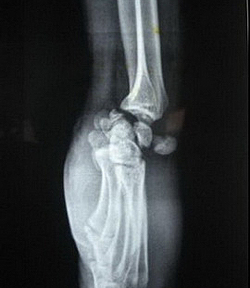

Перилунарные вывихи кисти

Составляют около 90% от общего числа вывихов кисти. Возникают при падении с упором на кисть или резком насильственном разгибании кисти. При перилунарном вывихе кисти контакт между полулунной и лучевой костью сохраняется, а остальные кости запястья смещаются к тылу и к центру. Перилунарный вывих кисти иногда сопровождается переломами трехгранной, ладьевидной костей и шиловидных отростков.

Все тыльные вывихи сопровождаются выбуханием на тыле кисти и сгибанием пальцев. При сдавлении срединного нерва выявляется нарушение чувствительности в зоне иннервации. Окончательный диагноз устанавливается на основании рентгенограмм в двух, а в сомнительных случаях – в трех проекциях.